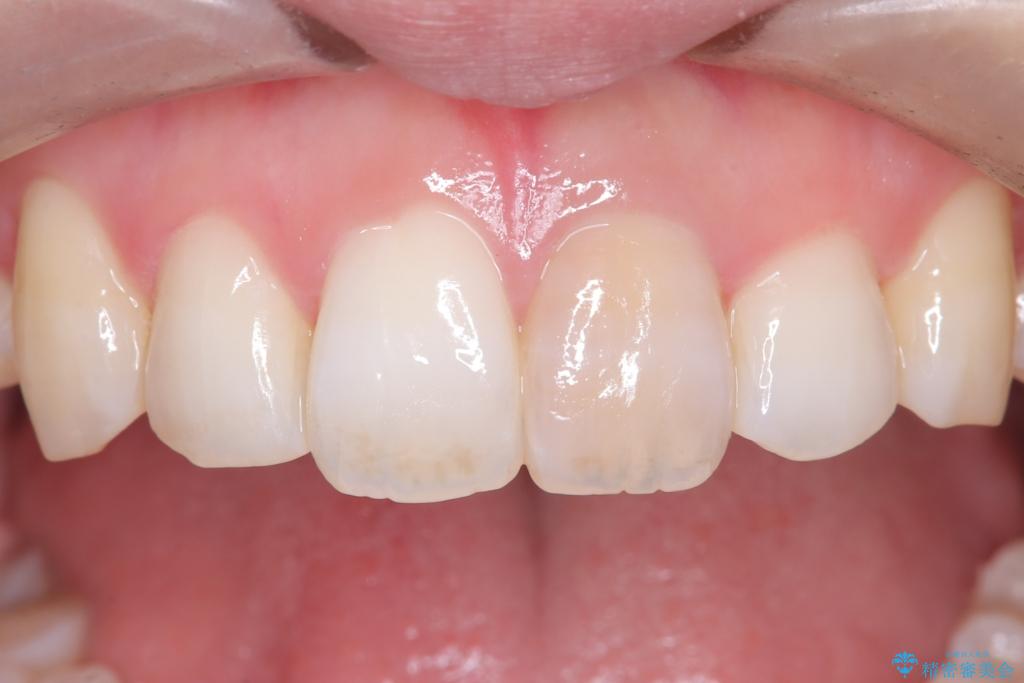

そこで、まずは土台を外して根の内部をきれいにする再根管治療を行い、基礎をやり直した上で、透明感の高いオールセラミッククラウンで被せ直す治療計画を立案。単に白くするだけでなく、再発を防ぎ、長期的に美しい状態を保つことを目指しました。

オールセラミッククラウンによる修復: 最終的な被せ物には、一切の金属を使用しないオールセラミックを選択。隣の天然歯と色調や透明感を精密に合わせることで、どこを治療したかわからないほど自然な仕上がりとなりました。